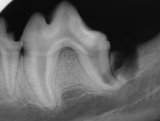

Enamel defect on a dog's molar

Enamel defect of lower left first molar. Abnormally shaped second molar. The third molar apparently is missing.